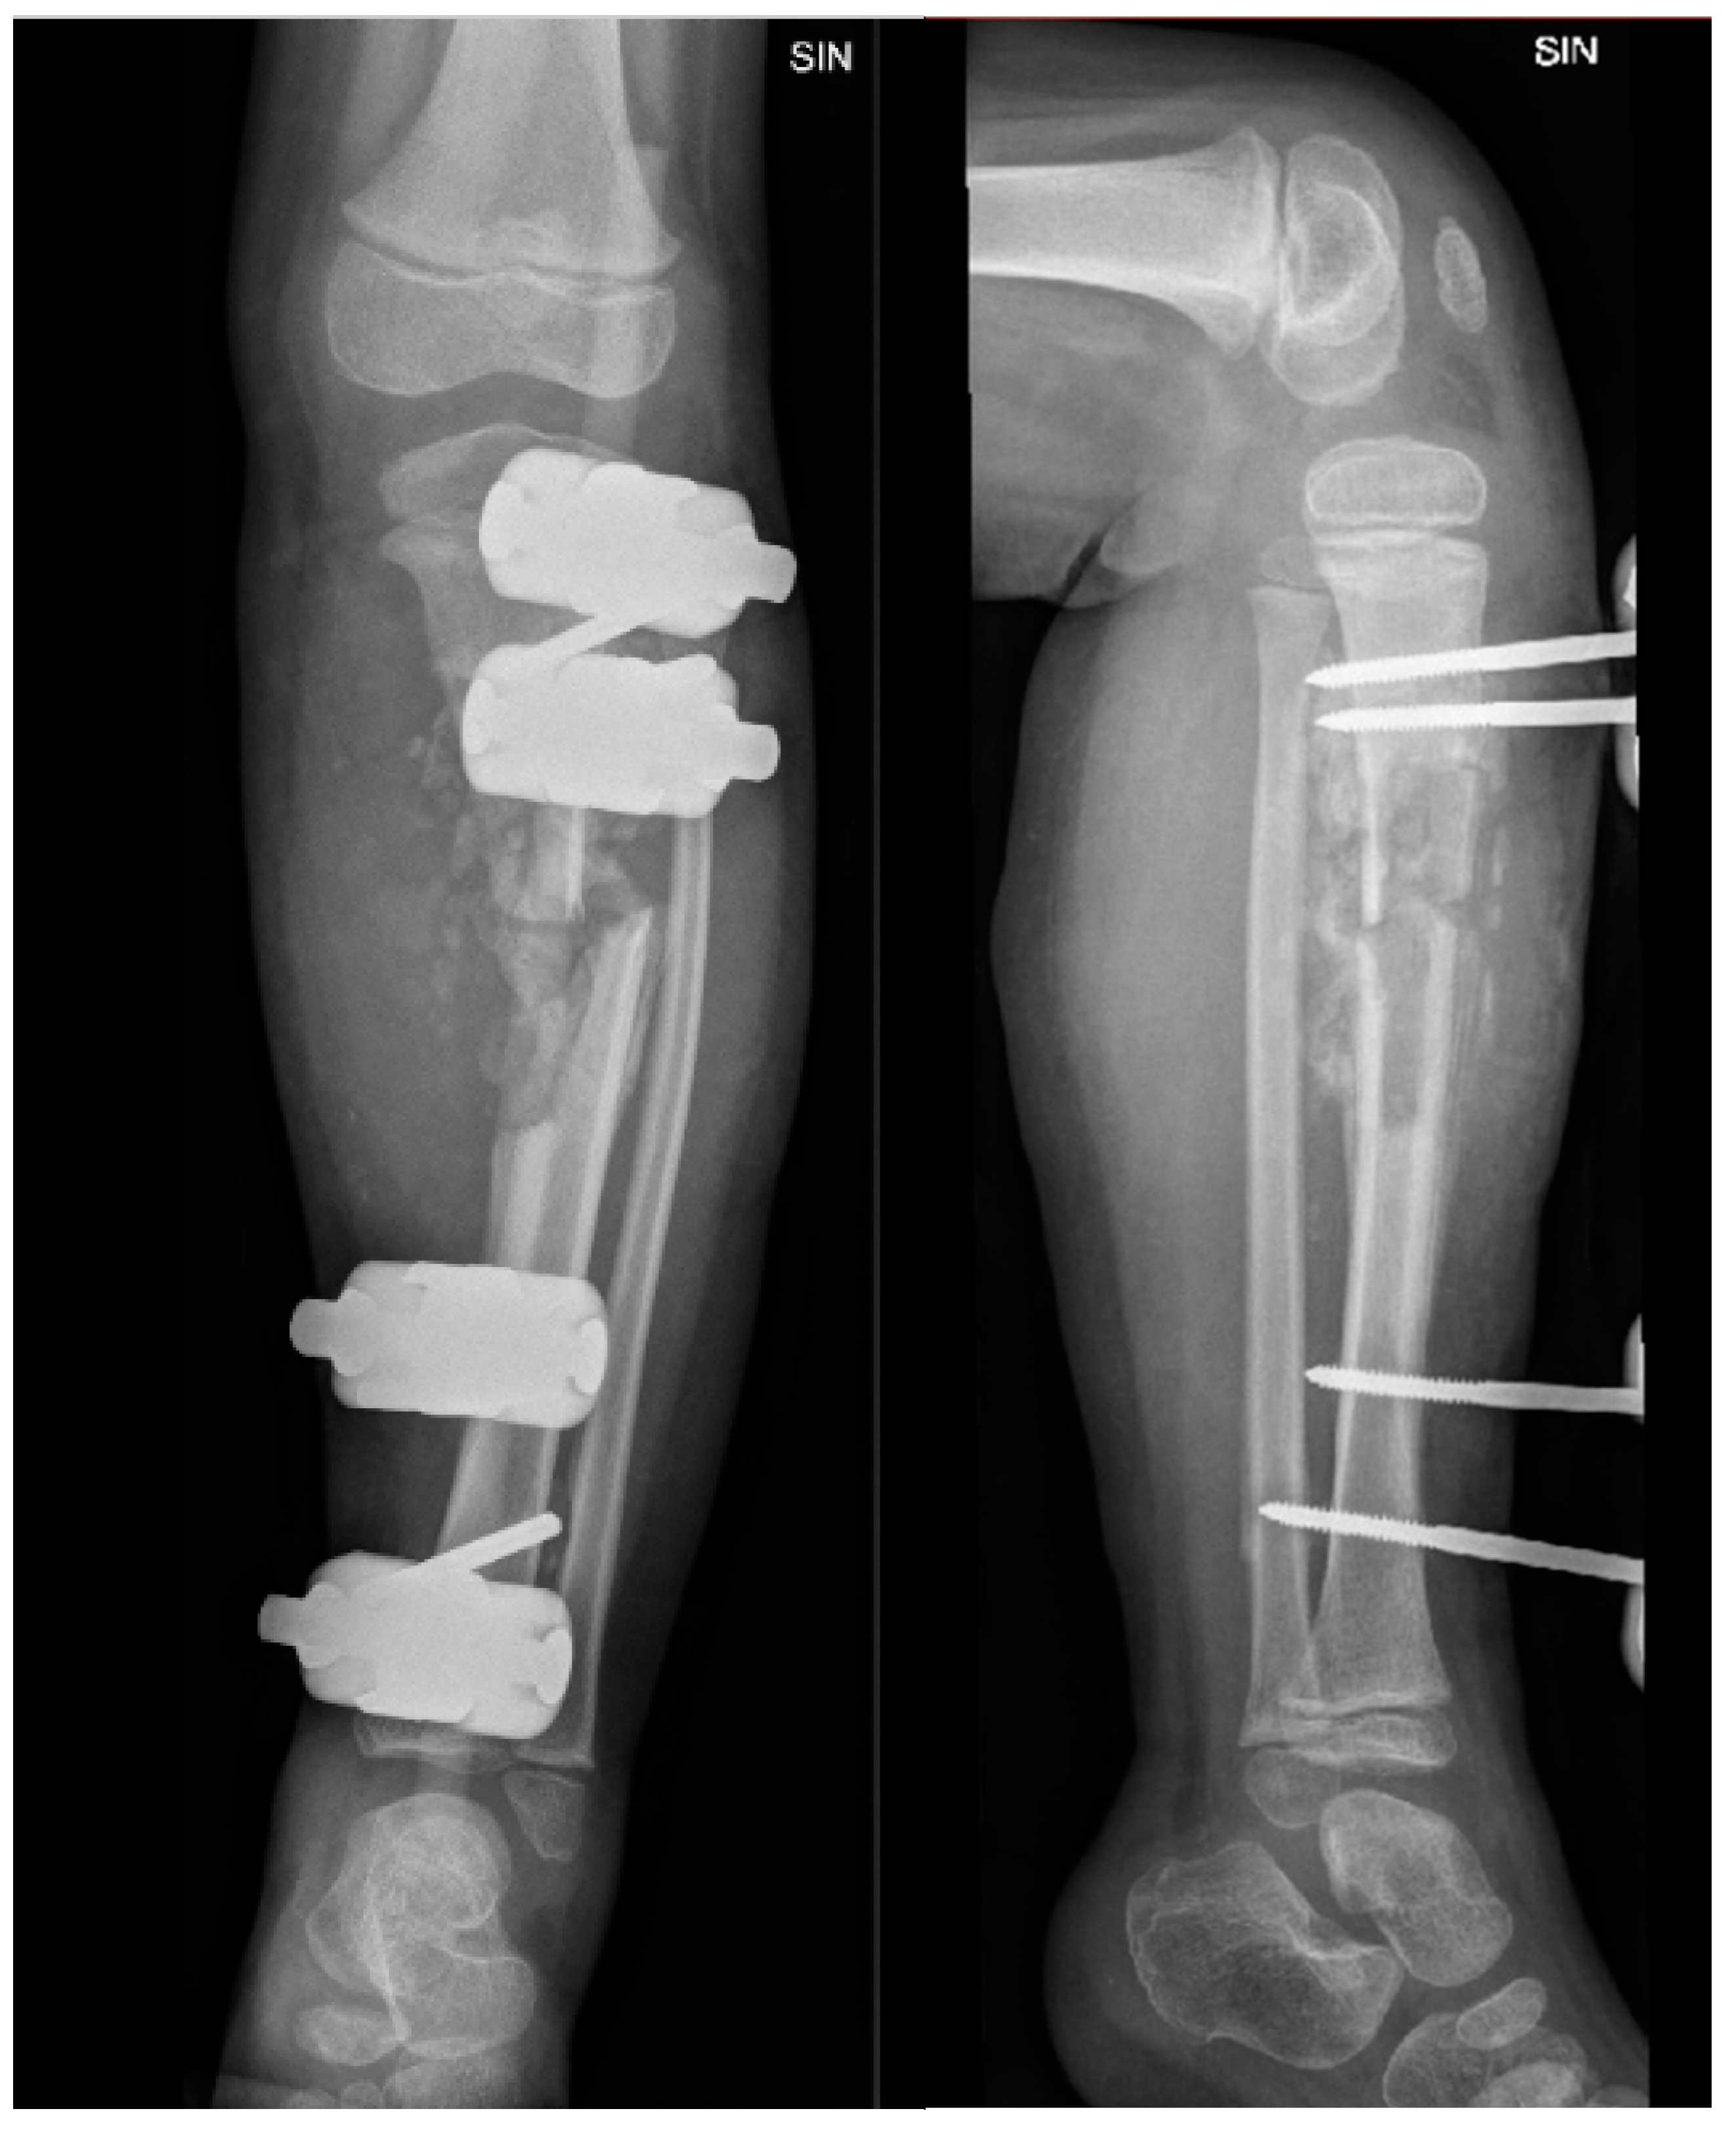

Considering the nature and extent of the changes, the complexity of the condition (Figure 11, Figure 12 and Figure 13), the patient was discussed at the council of surgeons and radiologists, where it was decided that reconstructive surgery was impossible and recommended considering the possibility of amputation for parents.

Figure 11. The X-ray examination of the distal third of the thigh in AP and lateral projections shows a condition after posttraumatic chronic osteomyelitis of the left tibial diaphysis. For the left thigh - the picture corresponds to the condition after an epiphyseal fracture in the anamnesis, the lateral condyle of the femur is of small volume, heterogeneous structure. Massive calcification paraosseous to diaphysis of femur.

Figure 12. X-ray examination of the proximal part of the left foot and the distal third of the lower leg in AP and lateral projections shows a condition in the left foot and lower leg after a plate fixation and implantation of a resected fibula diaphysis fragment. The area is not fully covered, and intense humming has developed after distal tibial osteoepiphysiolysis. Slight deformation in the metaphysis of the fibula remnant is also present.

Figure 13. X-ray examination of the left foot in AP and lateral projections. A fracture of the distal metaphysis of the second metatarsal bone of the left foot is visible without dislocation.